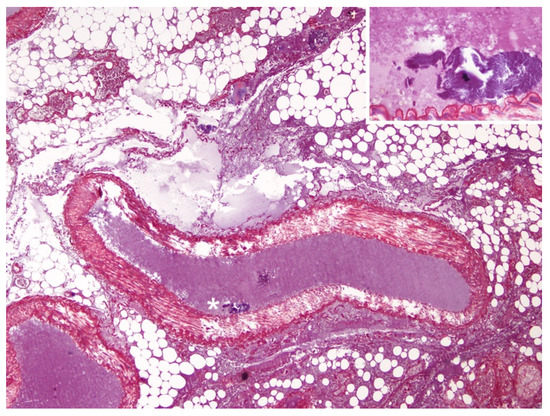

3.2. Histopathological and Histochemical Findings

3.3. Immunohistochemical Findings